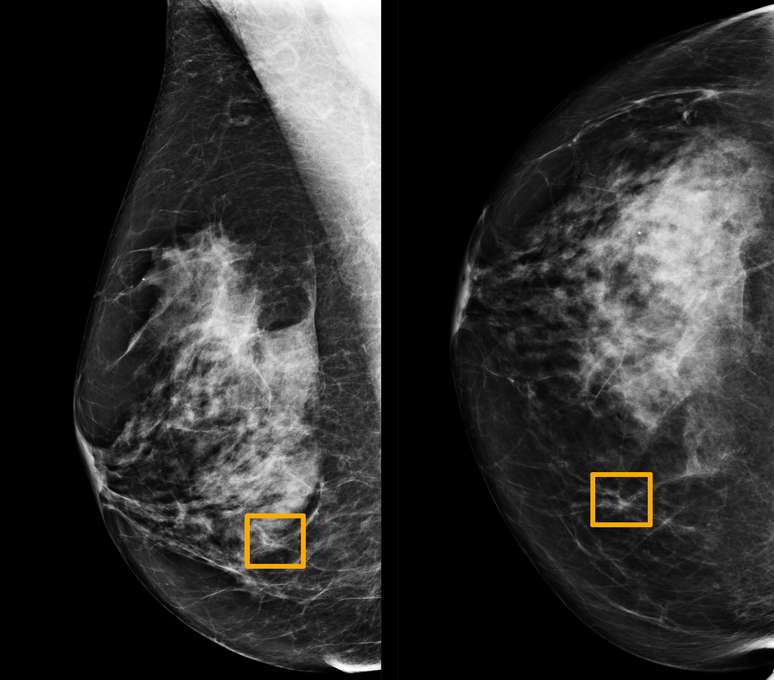

Um quadraro amarelo indica onde um sistema de inteligência artificial (IA) encontrou câncer escondido dentro do tecido mamário

Um quadraro amarelo indica onde um sistema de inteligência artificial (IA) encontrou câncer escondido dentro do tecido mamário 01/01/2020 Northwestern University/Divulgação via REUTERS